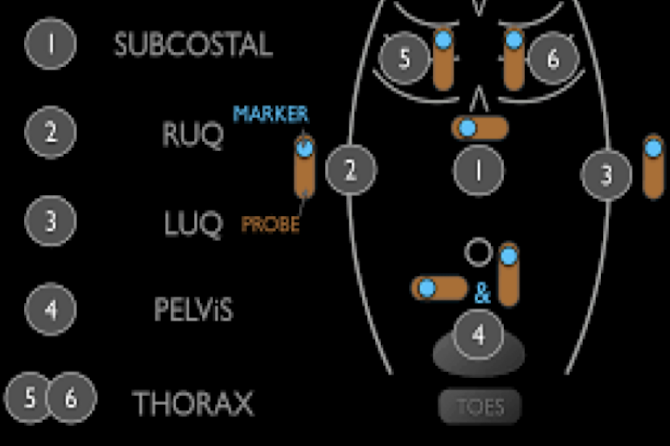

E-FAST (Extended Focused Assessment with Sonography in Trauma)

bedside ultrasound protocol design to detect peritoneal fluid, pericardial fluid, pneumothorax and/or hemothorax in trauma patient

RUSH Exam

ultrasound to quickly assess any patient with undifferentiated shock and hypertension